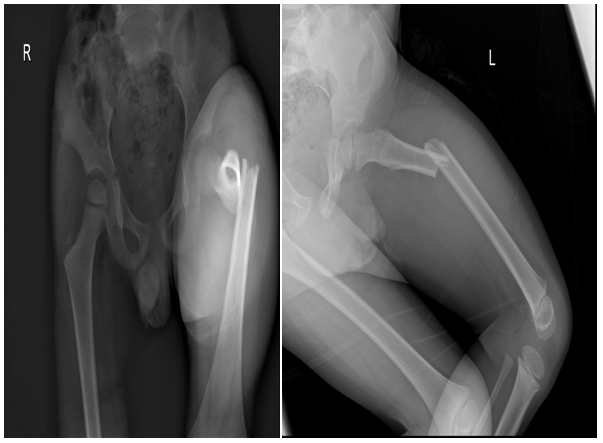

As part of primary survey patient’s chest and pelvis X-rays done at trauma bay shows no abnormality. AP and lateral X-rays of left femur showing hip and knee joints were reviewed by different ranked orthopaedics surgeons with agreement of normal x-ray impression (Figure 1 & 2). The following visits for the same complain has different x-rays with same impression of normal x-ray (Figure 3). Except for the one at last visit with the clinical evidence of deformity, patient has diaphysial femur fracture (Figure 4 ).

Figure 3 Different x-rays with same impression of normal x-ray.